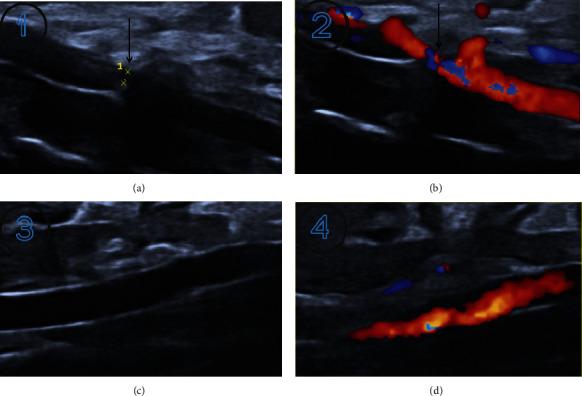

Heart failure is a complex clinical syndrome in which ventricular filling or ejection capacity is impaired due to structural or functional diseases of the heart. In order to establish a stable heart failure model, we investigated cardiac parameters in rats with abdominal aortic contraction and normal rats, including the left ventricular posterior wall diameter (LVPWd), the interventricular septum thickness of end-diastolic (IVSd), the left ventricular end-diastolic diameter (LVEDd), the left ventricular ejection fraction (LVEF), and left ventricular fractional shortening (LVFS). Rats were randomly divided into experimental group ( = 20) and control group ( = 20). The experimental group underwent modified abdominal aortic constriction, while the control group only isolated the abdominal aorta without constriction. The results showed that the survival rate of rats in the experimental group was 85% after one week of operation, while the survival rate of rats in the control group was 100%. Five weeks after operation, the left ventricular posterior wall diameter (LVPWd) and the interventricular septum thickness of end-diastolic (IVSd) in the experimental group were all increased compared with those in the control group, and the differences were statistically significant ( < 0.05); the left ventricular end-diastolic diameter (LVEDd) in the experimental group showed an increasing trend compared with the control group, but > 0.05; compared with the control group, the left ventricular ejection fraction (LVEF) and left ventricular fractional shortening (LVFS) in the experimental group showed downward trend, but > 0.05. 10 weeks after operation, the LVPWd, IVSd, and LVEDd of the experimental group were increased compared with the control group, < 0.05, and the LVEF and LVFS of the experimental group were decreased compared with the control group, < 0.05. Compared with the control group, the BNP of the experimental group increased significantly, < 0.05. The heart weight index and left ventricular weight index of rats in the experimental group were significantly higher than those in the control group, < 0.05. HE staining showed that the myocardial cells in the experimental group increased in volume, disordered cell arrangement, widened gaps, increased nuclear hyperchromia, and uneven staining. This paper provides a theoretical basis for the study of heart failure.

心力衰竭是一种复杂的临床综合征,由于心脏的结构或功能疾病,心室充盈或射血能力受损。为了建立稳定的心力衰竭模型,我们研究了腹主动脉缩窄大鼠和正常大鼠的心脏参数,包括左心室后壁直径(LVPWd)、舒张末期室间隔厚度(IVSd)、左心室舒张末期直径(LVEDd)、左心室射血分数(LVEF)和左心室短轴缩短率(LVFS)。大鼠随机分为实验组(n=20)和对照组(n=20)。实验组行改良腹主动脉缩窄,对照组仅分离腹主动脉而不缩窄。结果显示,术后一周实验组大鼠存活率为 85%,对照组大鼠存活率为 100%。术后 5 周,实验组大鼠左心室后壁直径(LVPWd)和舒张末期室间隔厚度(IVSd)均较对照组升高,差异有统计学意义(<0.05);实验组大鼠左心室舒张末期直径(LVEDd)较对照组呈增高趋势,但>0.05;与对照组相比,实验组大鼠左心室射血分数(LVEF)和左心室短轴缩短率(LVFS)呈下降趋势,但>0.05。术后 10 周,实验组大鼠 LVPWd、IVSd 和 LVEDd 较对照组升高,<0.05,LVEF 和 LVFS 较对照组降低,<0.05。与对照组相比,实验组大鼠 BNP 明显升高,<0.05。实验组大鼠心脏重量指数和左心室重量指数明显高于对照组,<0.05。HE 染色显示实验组大鼠心肌细胞体积增大,细胞排列紊乱,间隙增宽,核深染,染色不均。本文为心力衰竭的研究提供了理论依据。